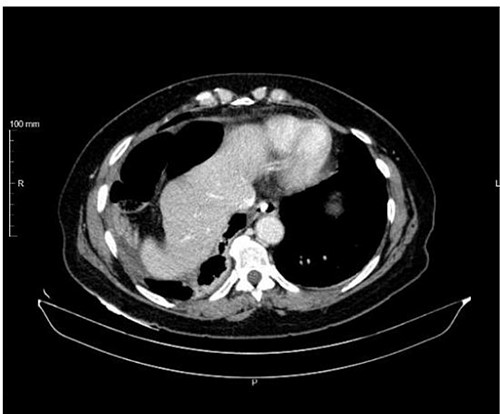

The patient underwent exploratory laparotomy, and there was a right diaphragmatic hernia with an intestinal loop in the chest. The hernia orifice was enlarged and the jejunal loop was reduced, which was necrotic without perforation (Fig. 3). Segmental enterectomy with later-lateral anastomosis was performed and a diaphragmatic repair was done with non-resorbable suture thread (Fig. 4). The abdominal and the right pleural cavities were washed and a chest tube was placed in the fifth intercostal space.